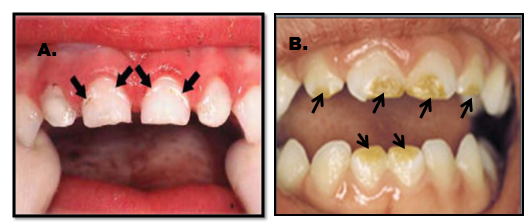

Vrlo je važno da se razlikuje karijes od razvojnog defekta. Karijes se pojavljuje kao bela mrlja na prethodno normalnoj gleđi i to pre svega uz ivicu desni. Rezvojni defekat je uglavnom na drugim površinama, gde se karijes ne javlja. (Slika 4. i 4b)

Karijes se uvek javlja uz desni i počinje kao bela mrlja(desno), razvojni defekti(hipoplazija) su češće na drugim delovima zuba(levo)

Karijes kod beba brzo napreduje i razara celu površinu zuba, pa ponekada može da podseća i na razvojne defekte.